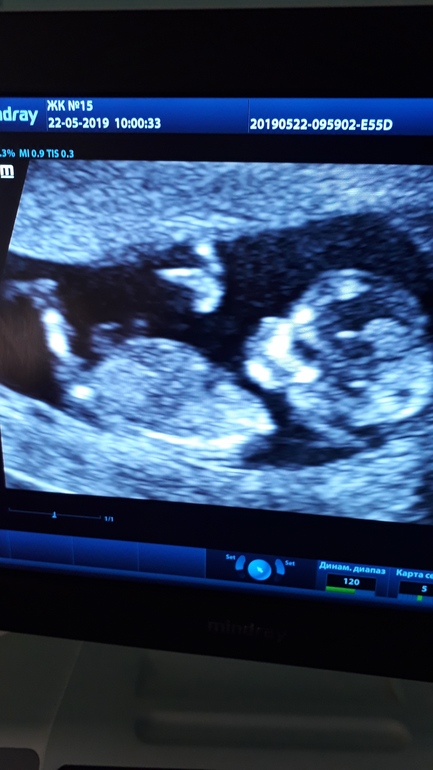

УЗИ, КТГ, доплерВсем привет! Сегодня у нас 12 и 5. Ходили на первый скрининг. Детка сначала решила потанцевать, потом повернулась ко всем попой и затихла ))) Хорошо, что успели сфотографировать и померить: КТР - 61 мм, ТВП - 1,5 мм, чсс - 172, носовая кость хорошо визуализируется. Еще мы сдали кровь. Надеюсь, кровь будет такая же хорошая, как и УЗИ.

Ну и пол.... вроде как девочка, но врач не была уверенна в этом вопросе... ) Если кто-то что-то увидит, буду рада мнениям )